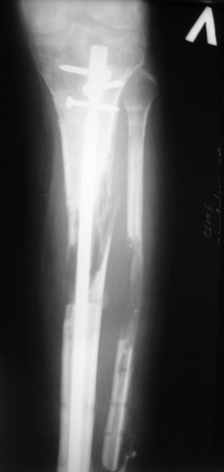

Ерсин, мы тоже имеем опыт такой фиксации. Подобную операцию за последние 3 года мы сделали трем пациентам. Снимки одного из них я прилагаю.

К сожалению, ни в одном из этих 3-х случаев мы не получили удовлетворяющего нас результата. Очень трудно провести штифт, введенный антеградно ровно по центру таранной кости. Отсутствие подвижности между диафизом и дистальным отломком большеберцовой кости (после фиксации в аппарате в течение 1-2 мес) очень усложняет проведение штифта в центр блока таранной кости. Поэтому мы от этого пока отказались, и проводим штифт через пятку. При данном варианте фиксации подобных проблем не возникало ни разу.